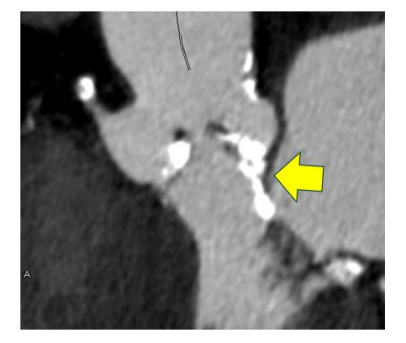

前向き肺動脈血流を伴う上大静脈―右肺動脈吻合に対する数値流体力学解析

概要

本報告は、前向き肺動脈血流を制限した上大静脈―右肺動脈(SVC–RPA)吻合術後の乳児症例について、数値流体力学(CFD)解析を用いて血行動態を評価したものである。残存する右肺動脈狭窄により前向き肺動脈血流が制限され、SVCにおける壁せん断応力およびエネルギー損失が低下するという良好な血行動態が示された。

症例

症例は1歳男児で、心室中隔欠損、心房中隔欠損、三尖弁低形成、および正常の約50%の大きさの小右室を有していた。SVC–RPA吻合、心室中隔欠損および心房中隔欠損閉鎖、肺動脈デバンディングを施行した。先行する肺動脈バンディングによる近位右肺動脈狭窄は、SVC血流と前向き肺動脈血流の競合を避ける目的で温存された。

分析方法

術後10か月時点で、画像データに基づく患者特異的CFD解析を行い、血流の流線、壁せん断応力、血流停滞、エネルギー損失などの詳細な血行動態評価を実施した。

結果

主肺動脈、左肺動脈、および近位右肺動脈では乱流および比較的高い壁せん断応力が認められた一方、SVCおよび遠位右肺動脈では平滑な層流、低壁せん断応力、血流停滞の最小化、低エネルギー損失が観察された。SVCおよび主肺動脈からの血流は競合することなく両肺へ分配され、バランスの取れた肺血流が維持されていた。